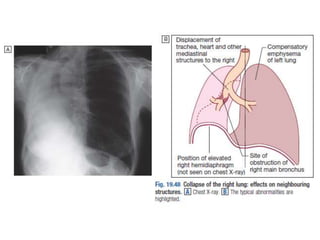

Collapsed Right Lung

Tension Pneumothorax: Requires chest tube

Tracheal Deviation

What would you do with this patient?

• 29.

• Chest X-rayPA view showing the sharply defined edge of the deflated lung with complete translucency (no lung markings, no vascular markings) between this and the chest wall in the Rt side with shifting of mediastinum to left. • Suggestive of Rt Tension Pneumothorax

• 32.

32 154 slides Collapsed RightLung Tension Pneumothorax: Requires chest tube Tracheal Deviation What would you do with this patient? 32